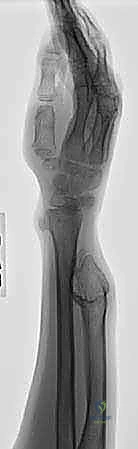

جراحة تشوهات الساعد والأورام العظمية الغضروفية الوراثية المتعددة (MHE): دليل المريض الشامل مع الأستاذ الدكتور محمد هطيف

دليل شامل للمرضى حول تشوهات الساعد الناتجة عن الأورام العظمية الغضروفية الوراثية المتعددة (MHE). تعرف على الأعراض والتشخيص وخيارات العلاج ا…